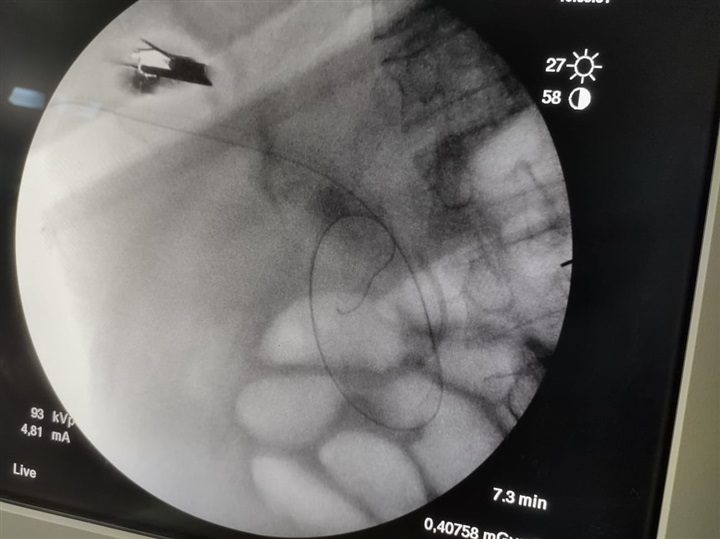

وقال بيان الهيئة: إنه تم إجراء عملية (راندڤو) ناجحة لمسن يعاني من صفراء انسدادية، وخلال العملية يتم استخدام المنظار والأشعة التداخلية معًا، وذلك لأول مرة تحت مظلة التأمين الصحي الشامل الجديدة، مشيرًا إلى أنه بمراجعة التاريخ المرضي للمنتفع، تبين أنه قام بإجراء عملية قلب مفتوح منذ ٧ أشهر، مع وجود فشل في وظائف القلب وارتجاع في الصمام المترالي.

وتابع البيان، تم عمل محاولتين لعمل منظار قنوات مرارية للمنتفع المشار إليه، وكانتا غير ناجحتين، وعليه تم تحضير المريض لإجراء عملية (راندڤو)، والتي تتم بمشاركة استشاري المناظير مع استشاري الأشعة التداخلية، وذلك لإزالة سبب انسداد القنوات الصفراوية مع تركيب دعامة له، وذلك تحت مظلة التأمين الصحي الشامل، دون تحميل المريض أكثر من 300 جنيه فقط نسبة مساهمة.

واستكمل الدكتور مصطفى شعبان، مدير فرع الهيئة ببورسعيد، أن مزايا عمليات المناظير عديدة لا تتوافر في الجراحات المفتوحة مثل سرعة التعافي وقِصر المكوث في المستشفى والعودة السريعة لممارسة الحياة الطبيعية، لافتًا أن تقنية (راندڤو) هي تقنية تجرى لأول مرة على أرض بورسعيد، وأطلق عليها هذا الاسم حيث يتلاقى المنظار والأشعة التداخلية داخل جسم المريض، بالمنطقة المصابة خلال العملية، مؤكدًا نجاح العملية وتماثل المريض للشفاء.